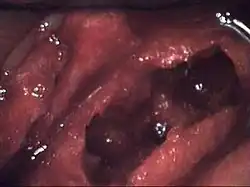

| Osteonecrosis of the jaw of the upper left jaw in a patient diagnosed with chronic venous insufficiency | |

The definitive symptom of ONJ is the exposure of mandibular or maxillary bone through lesions in the gingiva that do not heal.[4] Pain, inflammation of the surrounding soft tissue, secondary infection or drainage may or may not be present. The development of lesions is most frequent after invasive dental procedures, such as extractions, and is also known to occur spontaneously. There may be no symptoms for weeks or months, until lesions with exposed bone appear.[5] Lesions are more common on the mandible than the maxilla.